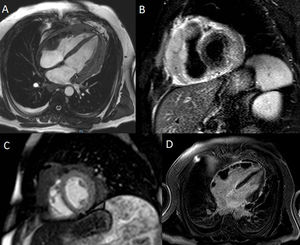

Tras estos hallazgos se decide realizar un cateterismo derecho no concluyente de constricción pericárdica (ausencia de hipertensión pulmonar, presiones telediastólicas biventriculares ligeramente elevadas, ausencia de Dip-meseta en ambos ventrículos, variaciones de presión no significativas). La sospecha diagnóstica en ese momento es de pericarditis constrictiva secundaria a la pericarditis tuberculosa previa. Con el fin de aclarar la disparidad de hallazgos entre cateterismo y ecocardiograma se realiza una resonancia magnética de corazón, sugestiva de linfoma con afectación cardiaca y extensión pericárdica, produciendo ligera constricción pericárdica (fig. 1).

A. Secuencia en sangre blanca, 4 cámaras donde se aprecian masas pericárdicas confluyentes e infiltrantes en pared lateral de VD y anillo tricuspídeo con señal intermedia en T1. B. Secuencia en T2-STIR, eje corto donde se aprecian masas pericárdicas en señal intermedia-baja en T2 y ligero derrame pericárdico. C. Secuencia de perfusión en reposo en eje corto objetivando perfusión no homogénea de las masas pericárdicas con focos necróticos o de baja captación. D. Secuencia de realce tardío en 4 cámaras con masas con ausencia de focos de fibrosis.